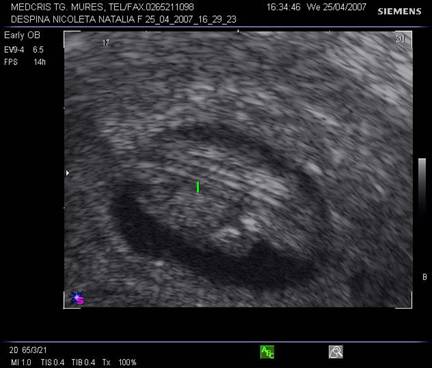

Fig nr. 8. Sarcina 5 sapt la ecografia transvaginala :sac ovular cu vezicula vitelina evidenta marcata cu sageata, retrouterin ovar chistic